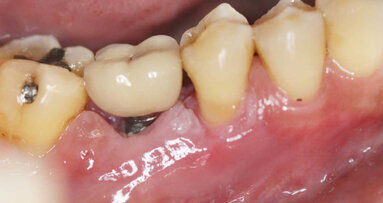

Pacijent u dobi od 66 godina doživio je traumu s posljedičnom frakturom korijena i palatinalnom dislokacijom zubi 11 i 21. Zubi su u okviru hitnog zbrinjavanja reponirani i splintirani (Slika 1.). Na pojedinačnoj rendgenskoj snimci zubi 11 i 21 uočava se intraalveolarni poprečni lom (Slika 2.). Prema aktualnim smjernicama takav lom u početku ne zahtijeva endodontsko liječenje ako se može isključiti da frakturna linija preko gingivnog sulkusa, odnosno parodontne pukotine komunicira s usnom šupljinom.

Budući da se to nije moglo isključiti za zub 21, u narednim posjetima provedeno je endodontsko liječenje s naknadnim punjenjem korijenskog kanala s MTA-om do pukotine (Slika 3.). Budući da je pacijent izrazio želju da se ne narušava estetika, za splintiranje je upotrijebljena palatinalna udlaga od PMMA-e (Slika 4.). Nakon tri mjeseca uočena je sve veća promjena boje zuba 21 i perzistentna pomičnost II. stupnja (Slika 5.). Nakon detaljnog informiranja o raznim mogućnostima liječenja kliničar i pacijent donijeli su odluku o implantoprotetskoj terapiji. CBCT snimljen tijekom planiranja terapije (Slika 6.), pokazao je blizak odnos prema vestibularnoj koštanoj lameli (položaj korijena I. razreda)14. Da bi se stvorio stabilan profil mekog i tvrdog tkiva i pacijentu što prije osigurao dobar estetski rezultat, kliničar se odlučio na imedijatnu implantaciju uz primjenu socket shield tehnike.

Slika 1. Početna situacija: Frontalni prikaz reponiranih i splintiranih zubi 11 i 21